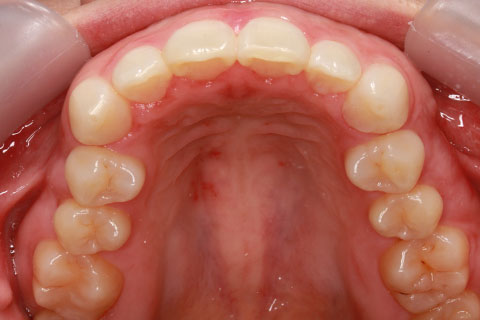

ハーフリンガル矯正3:上の歯のみ舌側矯正で治療(矯正期間24ヶ月)

治療前

治療中(開始直後)

治療中(開始半年後)

治療後

- 年齢・性別

- 25歳女性

- 治療期間

- 2年0ヶ月

- 抜歯

- 上下4番抜歯

- 治療費

- 110万円

- 治療内容

- 施術の副作用(リスク)

- 表側矯正と比較して、力学的な操作性が複雑なため、ボーイングエフェクトを起こしやすい。